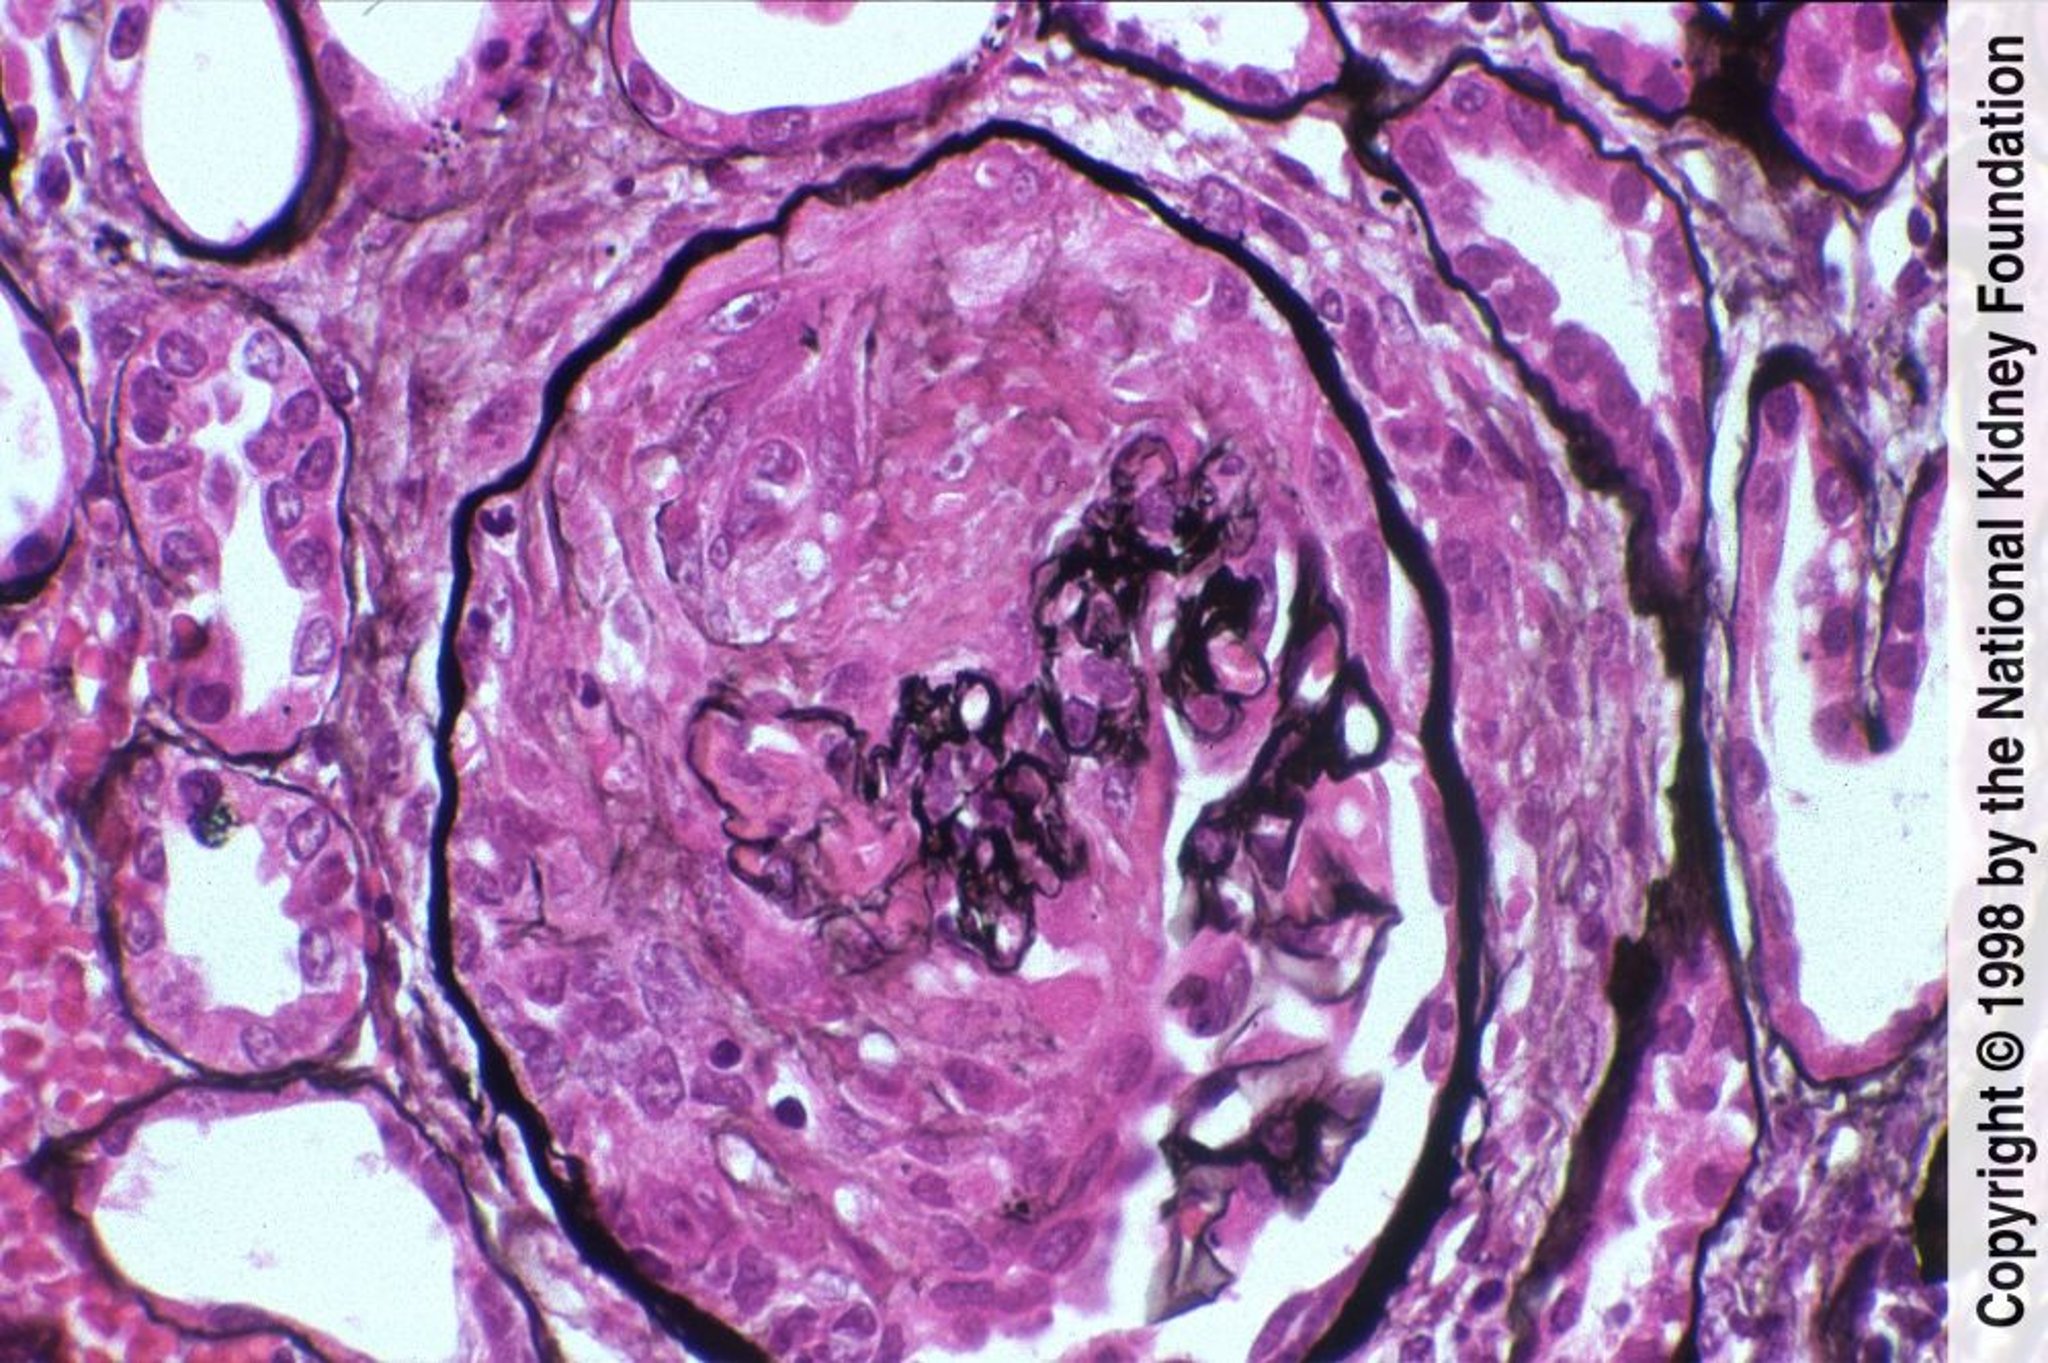

Glomerulonefritis de progresión rápida (Pauci-inmune)

La enfermedad pauciinmunitaria se caracteriza por la formación de medialunas con necrosis fibrinoide y tinción inmunofluorescente negativa (tinción de plata de Jones, ×400).

Image provided by Agnes Fogo, MD, and the American Journal of Kidney Diseases' Atlas of Renal Pathology (véase www.ajkd.org).